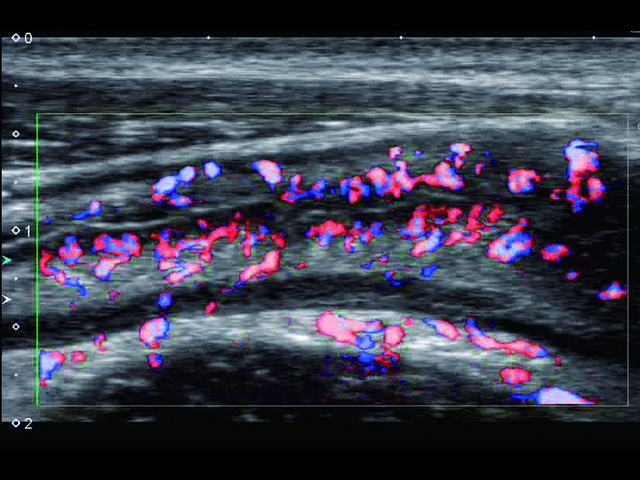

Обновленная версия легендарного УЗ-сканера. Стационарный аппарат экспертного класса Aplio 500 Toshiba NEW, визуализирует анатомические структуры в высоком разрешении. Модель позволяет выявить микрокальцификаты, новообразования, нарушения в работе сердца, сосудов и мышц. Присутствует функция виртуальной эндоскопии, 4D-сканирования, эластометрии тканей, УЗИ с контрастированием. За повышение качества изображения отвечают технологии ApliPure и Superb Microvascular Imaging. Первая задействует возможности пространственного и частотного кодирования, формирует цельный визуальный ряд с сохранением клинических маркеров. Вторая улучшает отображение микрососудистого русла, используя доплеровский эффект. Модель оснащена 21-дюймовым монитором, имеет 4 активных порта. Возможно подключение педиатрических, интраоперационных, лапароскопических и чреспищеводных датчиков.

• SMI. Опция, упрощающая визуализацию микроциркуляторного русла. С ее помощью обследуются сосуды с низкой интенсивностью кровотока, изучаются наиболее тонкие структуры. SMI упрощает диагностику новообразований, минимизирует вероятность ошибки.

Энергетический допплер:

Цветовой допплер:

Да